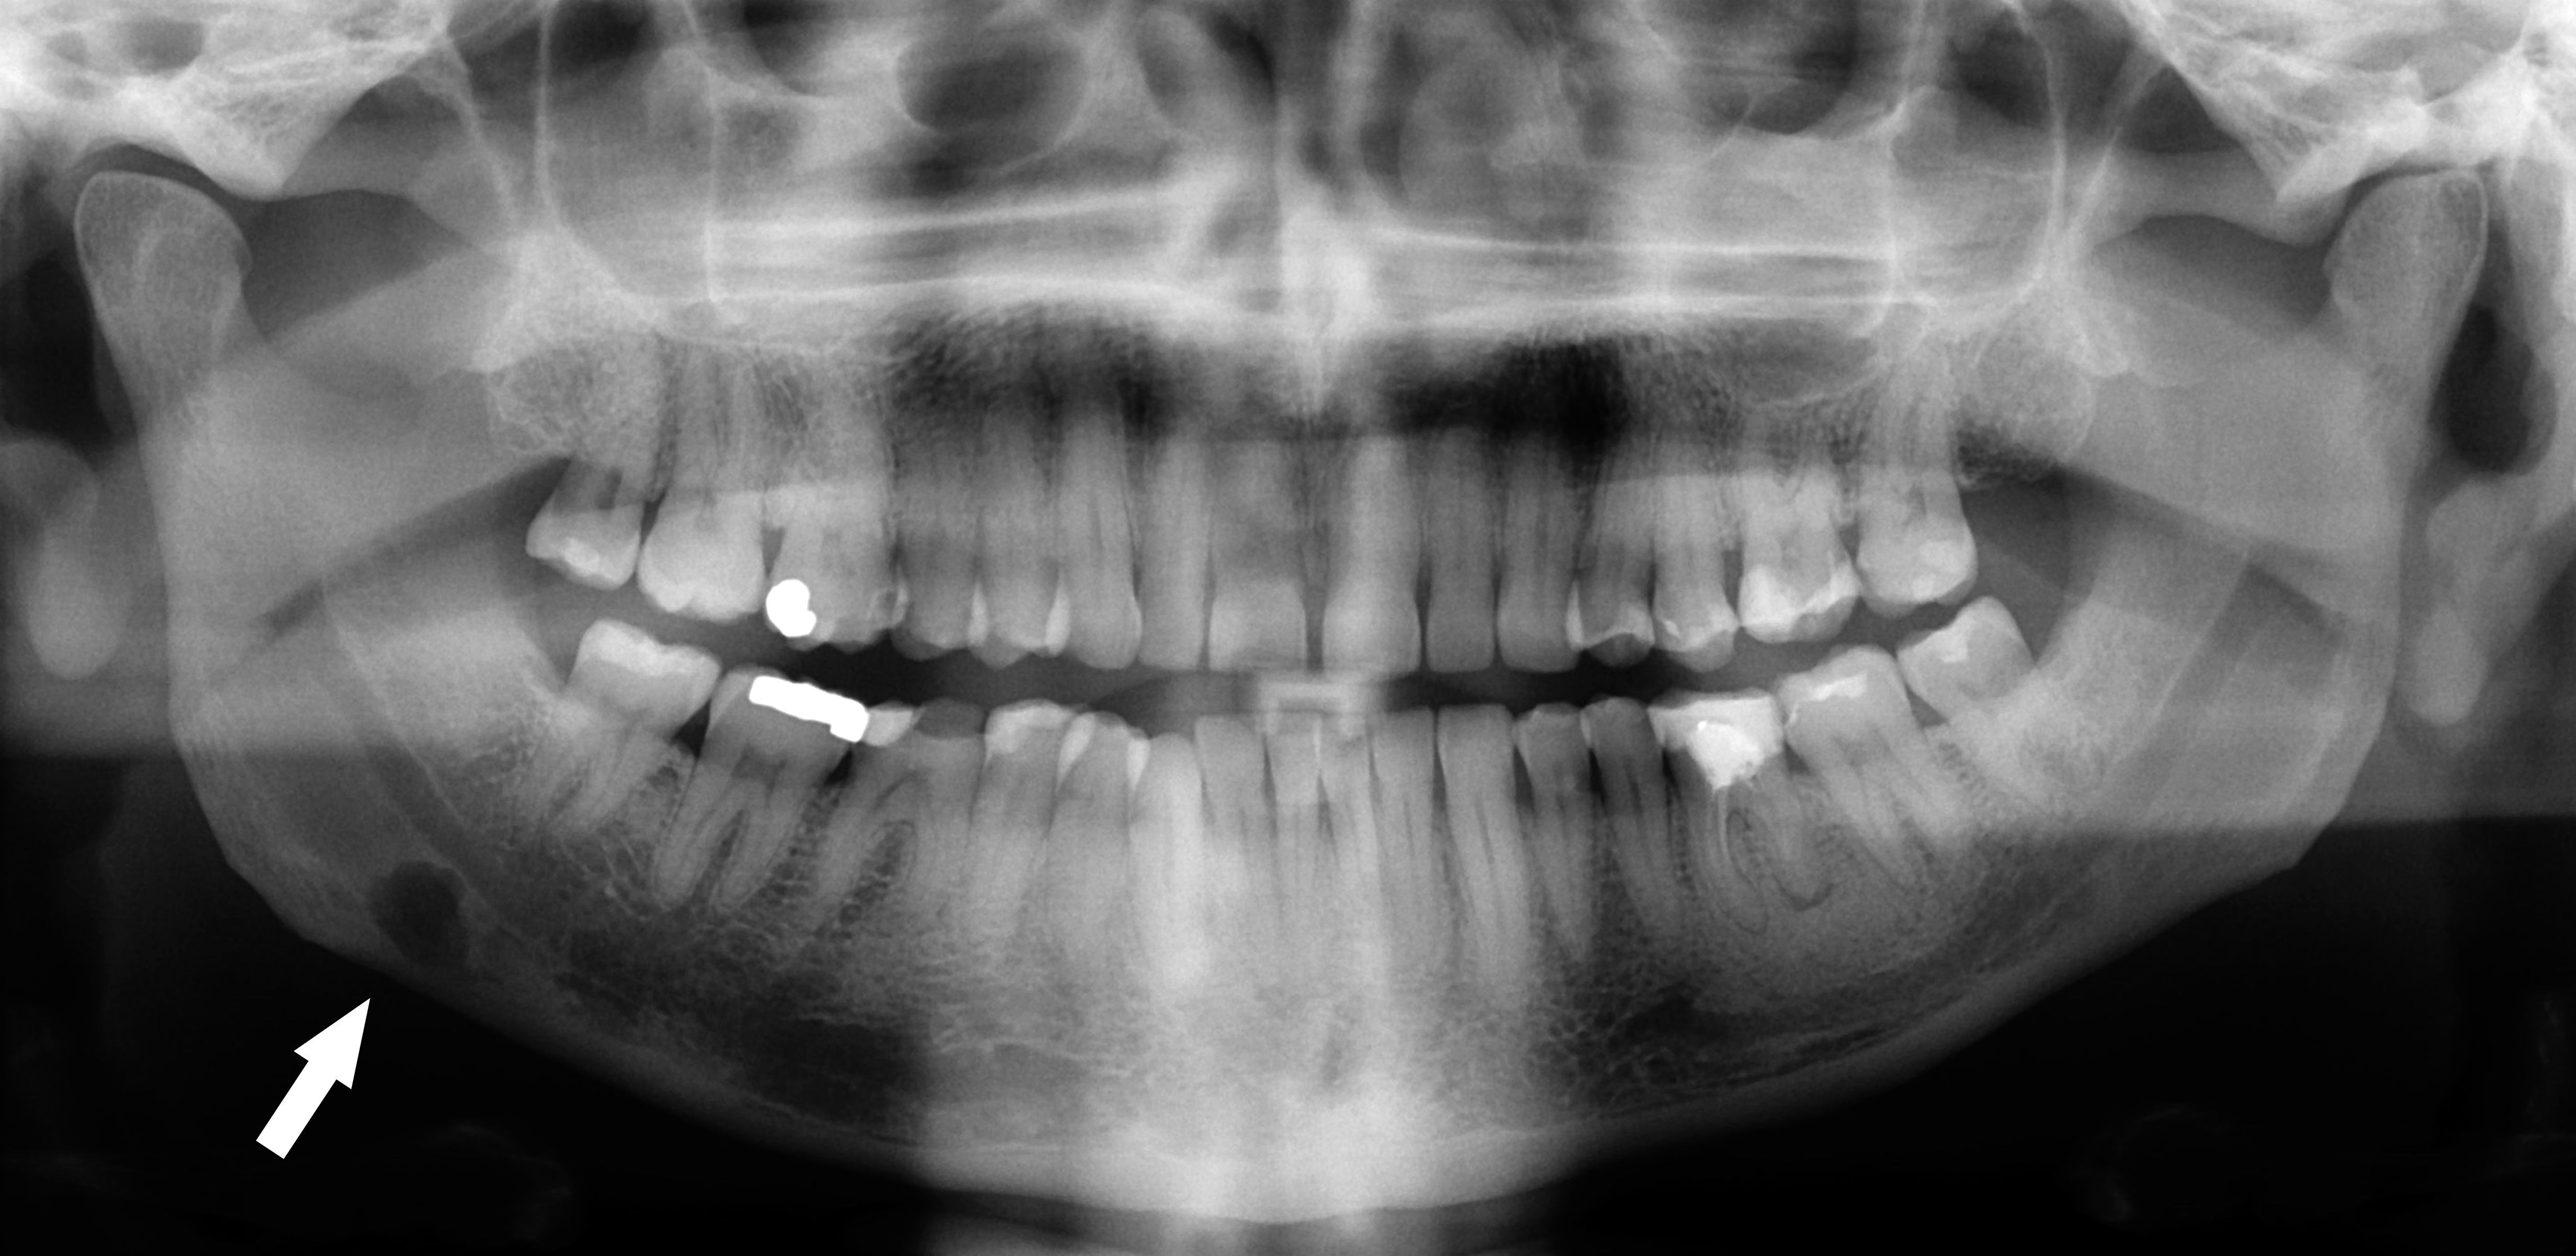

The Stafne defect (also termed Stafne's idiopathic bone cavity, Stafne bone cavity, Stafne bone cyst (misnomer), lingual mandibular salivary gland depression, lingual mandibular cortical defect, latent bone cyst, or static bone cyst) is a depression of the mandible, most commonly located on the lingual surface (the side nearest the tongue). The Stafne defect is thought to be a normal anatomical variant, as the depression is created by ectopic salivary gland tissue associated with the submandibular gland and does not represent a pathologic lesion as such.